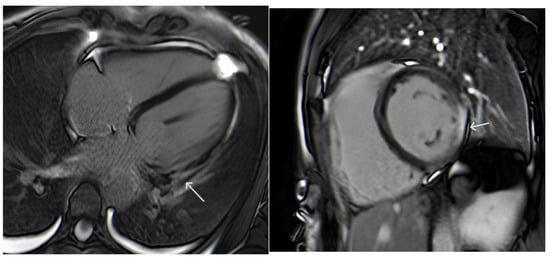

- Holmström, M.; Kivistö, S.; Heliö, T.; Jurkko, R.; Kaartinen, M.; Antila, M.; Reissell, E.; Kuusisto, J.; Kärkkäinen, S.; Peuhkurinen, K.; et al. Late gadolinium enhanced cardiovascular magnetic resonance of lamin A/C gene mutation related dilated cardiomyopathy. J. Cardiovasc. Magn. Reson. 2011, 13, 30. [Google Scholar] [CrossRef] [PubMed]